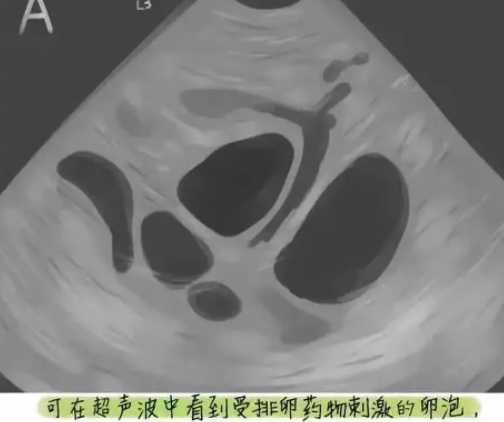

促排卵过程中通过B超监测卵泡生长情况结合激素变化调整促排卵药物,当卵泡发育成熟后给予扳机药物诱导卵母细胞成熟,一般在药物扳机后36小时行取卵术。